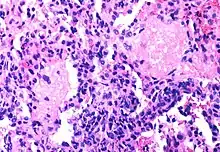

Although the fraction of CD4+ T-cells that is infected with HIV at any given time is never high (only a small subset of activated cells serve as ideal targets of infection), several groups have shown that rapid cycles of death of infected cells and infection of new target cells occur throughout the course of the disease.[39] Macrophages and other cell types are also infected with HIV and serve as reservoirs for the virus.

Furthermore, like other viruses, HIV is able to suppress the immune system by secreting proteins that interfere with it. For example, HIV's coat protein, gp120, sheds from viral particles and binds to the CD4 receptors of otherwise healthy T-cells; this interferes with the normal function of these signalling receptors. Another HIV protein, Tat, has been demonstrated to suppress T cell activity.

Infected lymphocytes express the Fas ligand, a cell-surface protein that triggers the death of neighboring uninfected T-cells expressing the Fas receptor.[40] This "bystander killing" effect shows that great harm can be caused to the immune system even with a limited number of infected cells.